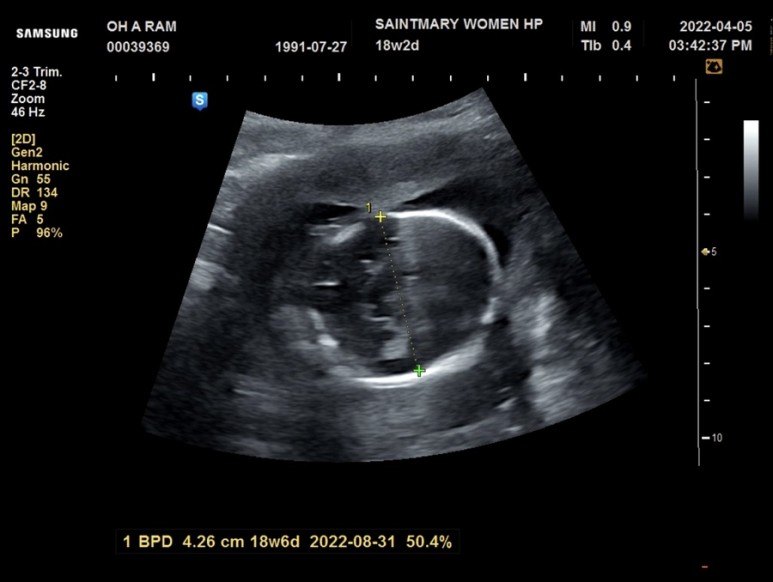

호랑이의 머리 둘레

호랑이의 허리 둘레

호람이 배를 보고 바로 놀란 그 이유는.. 호람이 주수에 비해 허리둘레가 너무 크고, 허리둘레가 큰 이유는 밀가루, 디저트 과일을 많이 먹었기 때문이라고 임신해서 밀가루, 과일을 정말 많이 먹었는데 그래서 호람이 허리둘레가 커졌다기보다

당분간 밀가루와 디저트는 먹지 말라고 하셨으니 주의하시는 게 좋겠다고…ㅎㅎ 청천벽력 같은 소리였다.

호랑이 다리 길이

호람이는 키도 잘 자라고 하셨는데 #10개월 후에 앱을 보니 호람이의 다리가 짧네. 그리고 성별도 확인! 매끈해서 공주라고 하셨는데 20주에 다시 확인해 보자구.딸한테서 아들에게 반전도 있다던데?호람아 20주에 미사일 나오는 거 아니지?